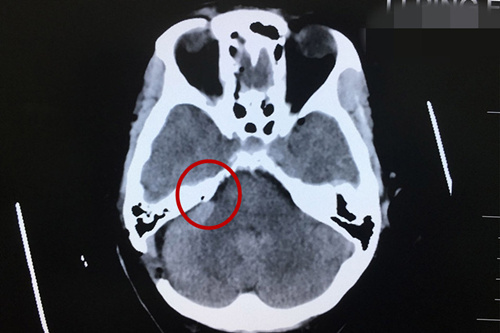

術(shù)后CT顯示:小腦及腦干形態(tài)如常,未見(jiàn)明顯異常密度病灶。